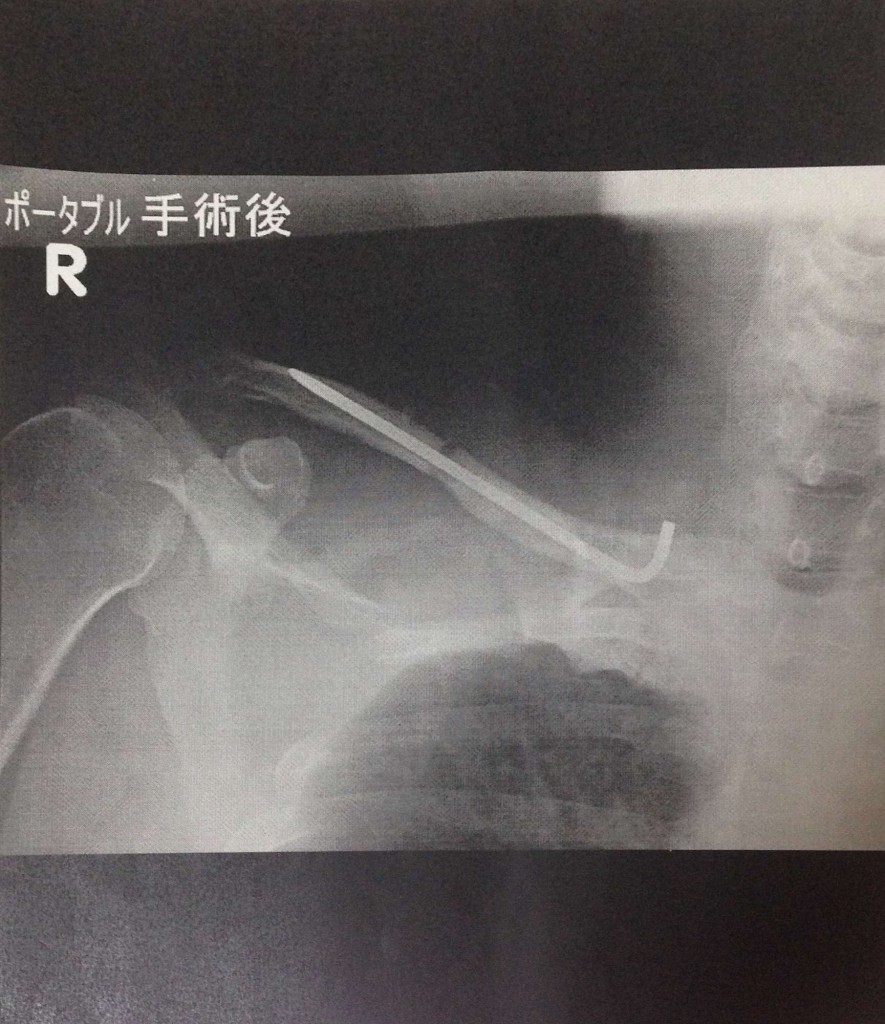

こちらは右肩鎖骨のピン留めの様子。ポキっとキレイに折れています。

手術でピンを骨の中へ通し止めています。たしか2−3ヶ月くらいで取り出す手術をする予定とのこと。右側の先が折れているところは少し肌を押し上げて皮膚が膨らんでいます。(この部分から引き抜くのかな?)